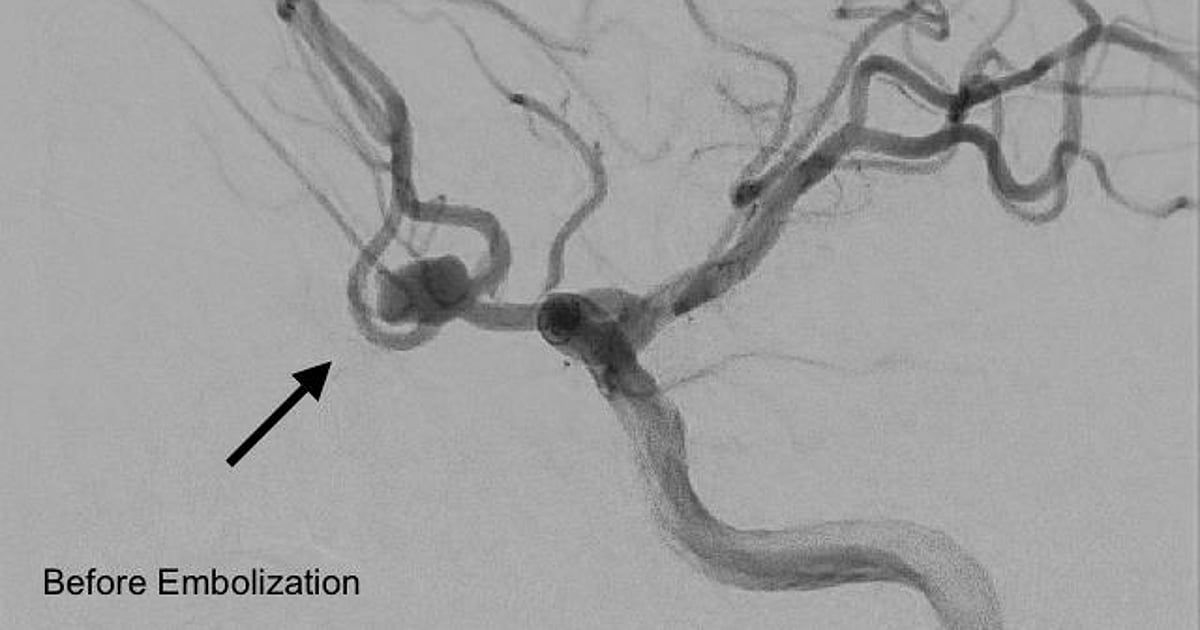

ونُفِّذ الإجراء بواسطة فريق التدخلات العصبية باستخدام ملفات معدنية دقيقة لإغلاق التمدد الشرياني، ما أسهم في السيطرة الكاملة على النزيف واستقرار حالة المريض واستعادته وعيه بالكامل.